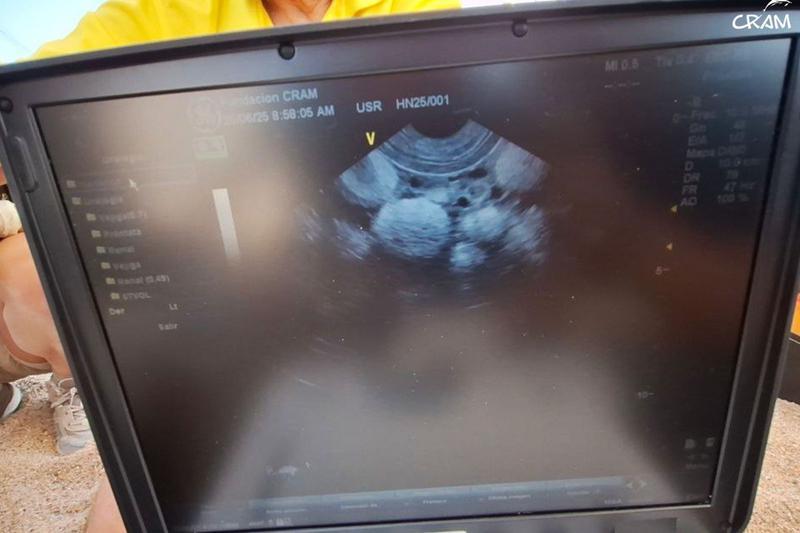

Els experts que s'han traslladat fins al lloc han pogut comprovar que el niu té 101 ous, que es mantindran tots a la platja perquè consideren que reuneix els requisits necessaris per al període d'incubació. Quan han arribat allà, a més, han pogut col·locar un dispositiu de seguiment satel·lital i un xip a la femella. Després, la tortuga ha tornat al mar.